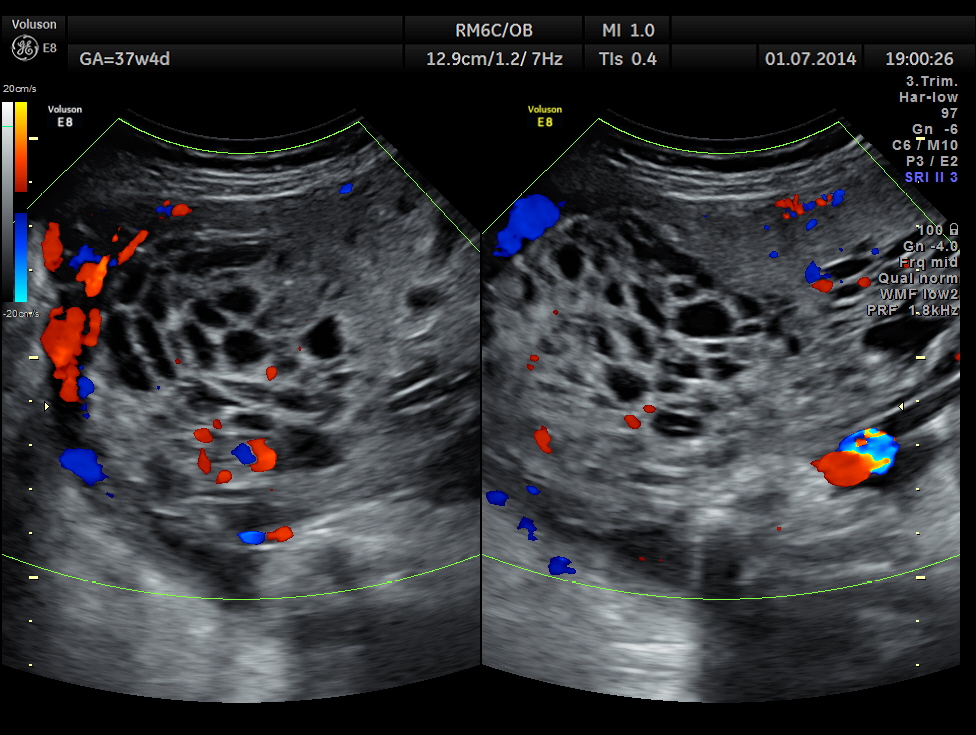

She came again after 2 months .The placenta appeared nearly the same , but showed more vascularity.

The spectral Doppler pictures are given below

Umbilical artery R.I . AND P.I. appear to be normal now. The cerebro placental ratio is also normal.